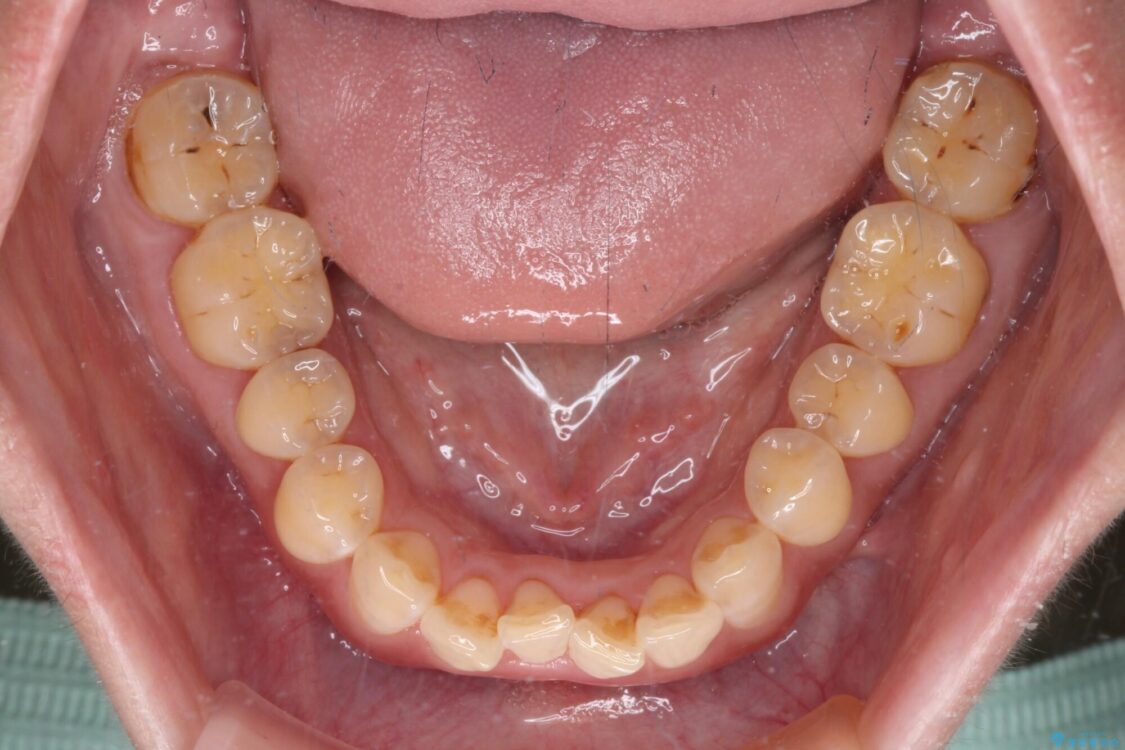

飛び出た上の前歯を気にして来院された患者様です。

奥歯の咬み合わせは、上顎歯列が理想的な一よりも数mm前方にある状態でした。

治療前

• 【モニター】飛び出た前歯を整えたい ワイヤー矯正治療 治療前画像